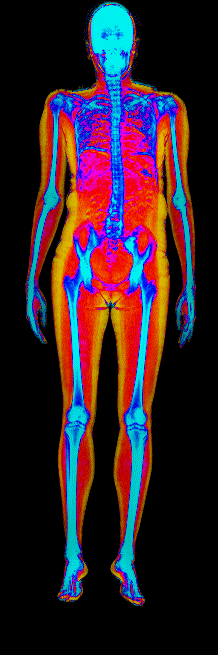

This page features real, anonymized DEXA scan images from BodyStats clients, organized by gender and body fat percentage in 5% increments. DEXA (Dual-Energy X-ray Absorptiometry) is the clinical gold standard for measuring body composition — far more accurate than scales, calipers, or visual estimates.

Each colorized scan shows the distribution of fat tissue (shown in warmer colors) and lean tissue (cooler colors) throughout the body. Compare your own DEXA scan to others in your range, or see what different body fat levels actually look like on a scan.

15 to 20% body fat

20 to 25% body fat